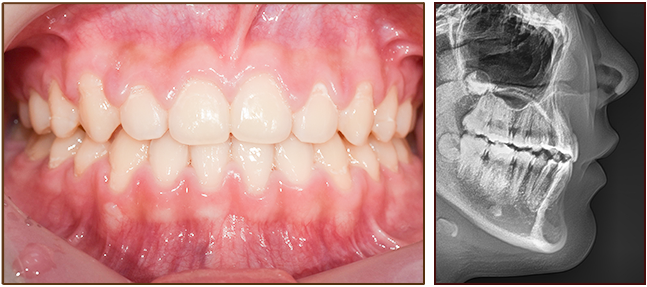

교정 전

교정 후